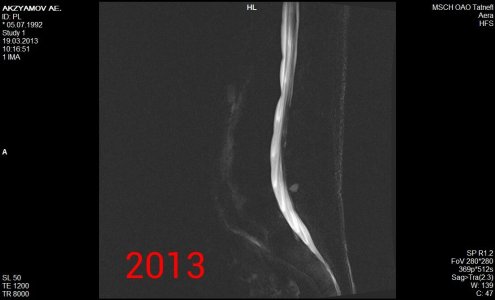

Здравствуйте! Я парень, мне 21 год, рост 190, вес 90, у меня поясничные грыжи l1-l2 1,8 мм, l2-l3 3,5 мм, l5-s1 4,4 мм, беспокоит уже 1,5 года слабость в ногах сначала была боль в левой ноге затем исчезла, и появилась постепенно слабость с внешней стороны квадрицепса до большого пальца ноги, и справа от колена по внешней стороне до большого пальца вниз, больше интересует непостоянность этих симптомов, то есть они могут вообще исчезать на один день и появляться на другой, могут появиться просто когда лежал телевизор смотрел и при этом спина вообще не болит, и в ногах боли тоже нет, невролог проводивший осмотр направлял на вич, гепатит, сифилис все чисто. Если начинаю пить прозерин по 2 таблетки в день все как рукой снимает. Ниже приведены все снимки и заключения имеющиеся на руках.Что это может быть, почему слабость может так быстро исчезать и появляться снова, грыжи то на месте может это что то другое? И еще хотелось бы узнать ваше мнение по поводу записи в заключении 2013 года (Арахноидальная киста в мягких тканях на уровне межостистых отростков L5-S1 7x8-8x2 мм) она не может сдавливать нервы?